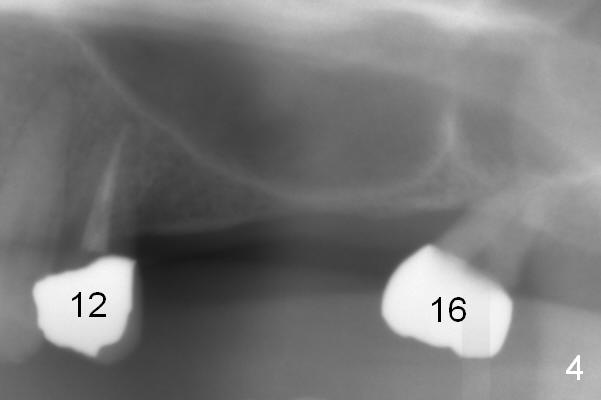

A 64-year-old man (MM) had caries at the tooth #12 (Fig.1), requiring root canal therapy (RCT, Fig.2). One year later, the periapical radiolucency reduces (Fig.3 <, as compared to that in Fig.2). The tooth remains asymptomatic 7 years posts RCT (Fig.4). A year later, the tooth has pain and buccal gingival swelling (probing tenderness); periradicular radiolucency is evident (Fig.5 arrowheads). It appears that the root fractures. Between the 7th and 8th years post RCT, the patient masticated mainly on the left side, while implants were placed at #30 and 31. The patient plans to have 4 implants in the upper left sextant (Fig.6). While implants are being placed at the site of #12 (Clindamycin) and 13, sinus lift seems mandatory at the sites of #13 and (initial depth will be 5-6 mm). By the time implants to be placed at #14 and #15, the bone height may increase.